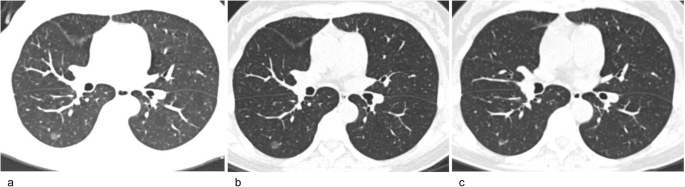

A 49-year-old woman with subsolid nodule growth after long-term follow-up CT. a Baseline CT. Transverse plain CT of a pure ground-glass nodule in the right lower lobe. The nodule size (longest diameter) was 8 mm on transverse CT images. b Follow-up CT obtained 5 years after baseline. The pure ground-glass nodule was stable. c Follow-up CT obtained 6 years after the baseline CT. A new solid component appeared in the nodule, and its size decreased from 8 to 6 mm. The growing nodule was a minimally invasive adenocarcinoma, as confirmed by pathology